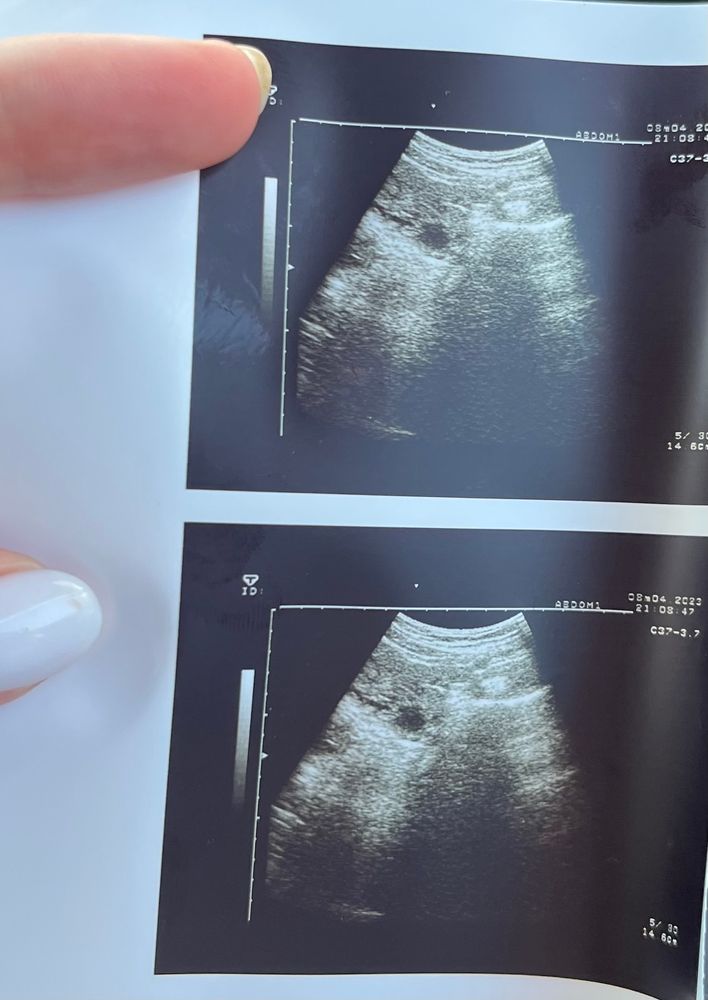

Девочки , кто разбирается , помогите расшифровать снимок

На узи доктор сказала , что это ещё не ЖТ , а фолликул с не четким контуром , есть небольшое количество жидкости в позадиматочном пространстве , получается овуляция происходит сейчас , лопается фолликул , или она была уже и ЖТ ещё не сформировалось ??? Размеры 17*18мм , эндометрий 9мм